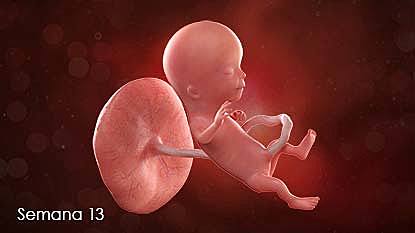

13

Semana 13

-Crece a 8,5 centímetros.

-El cartílago empieza a osificarse